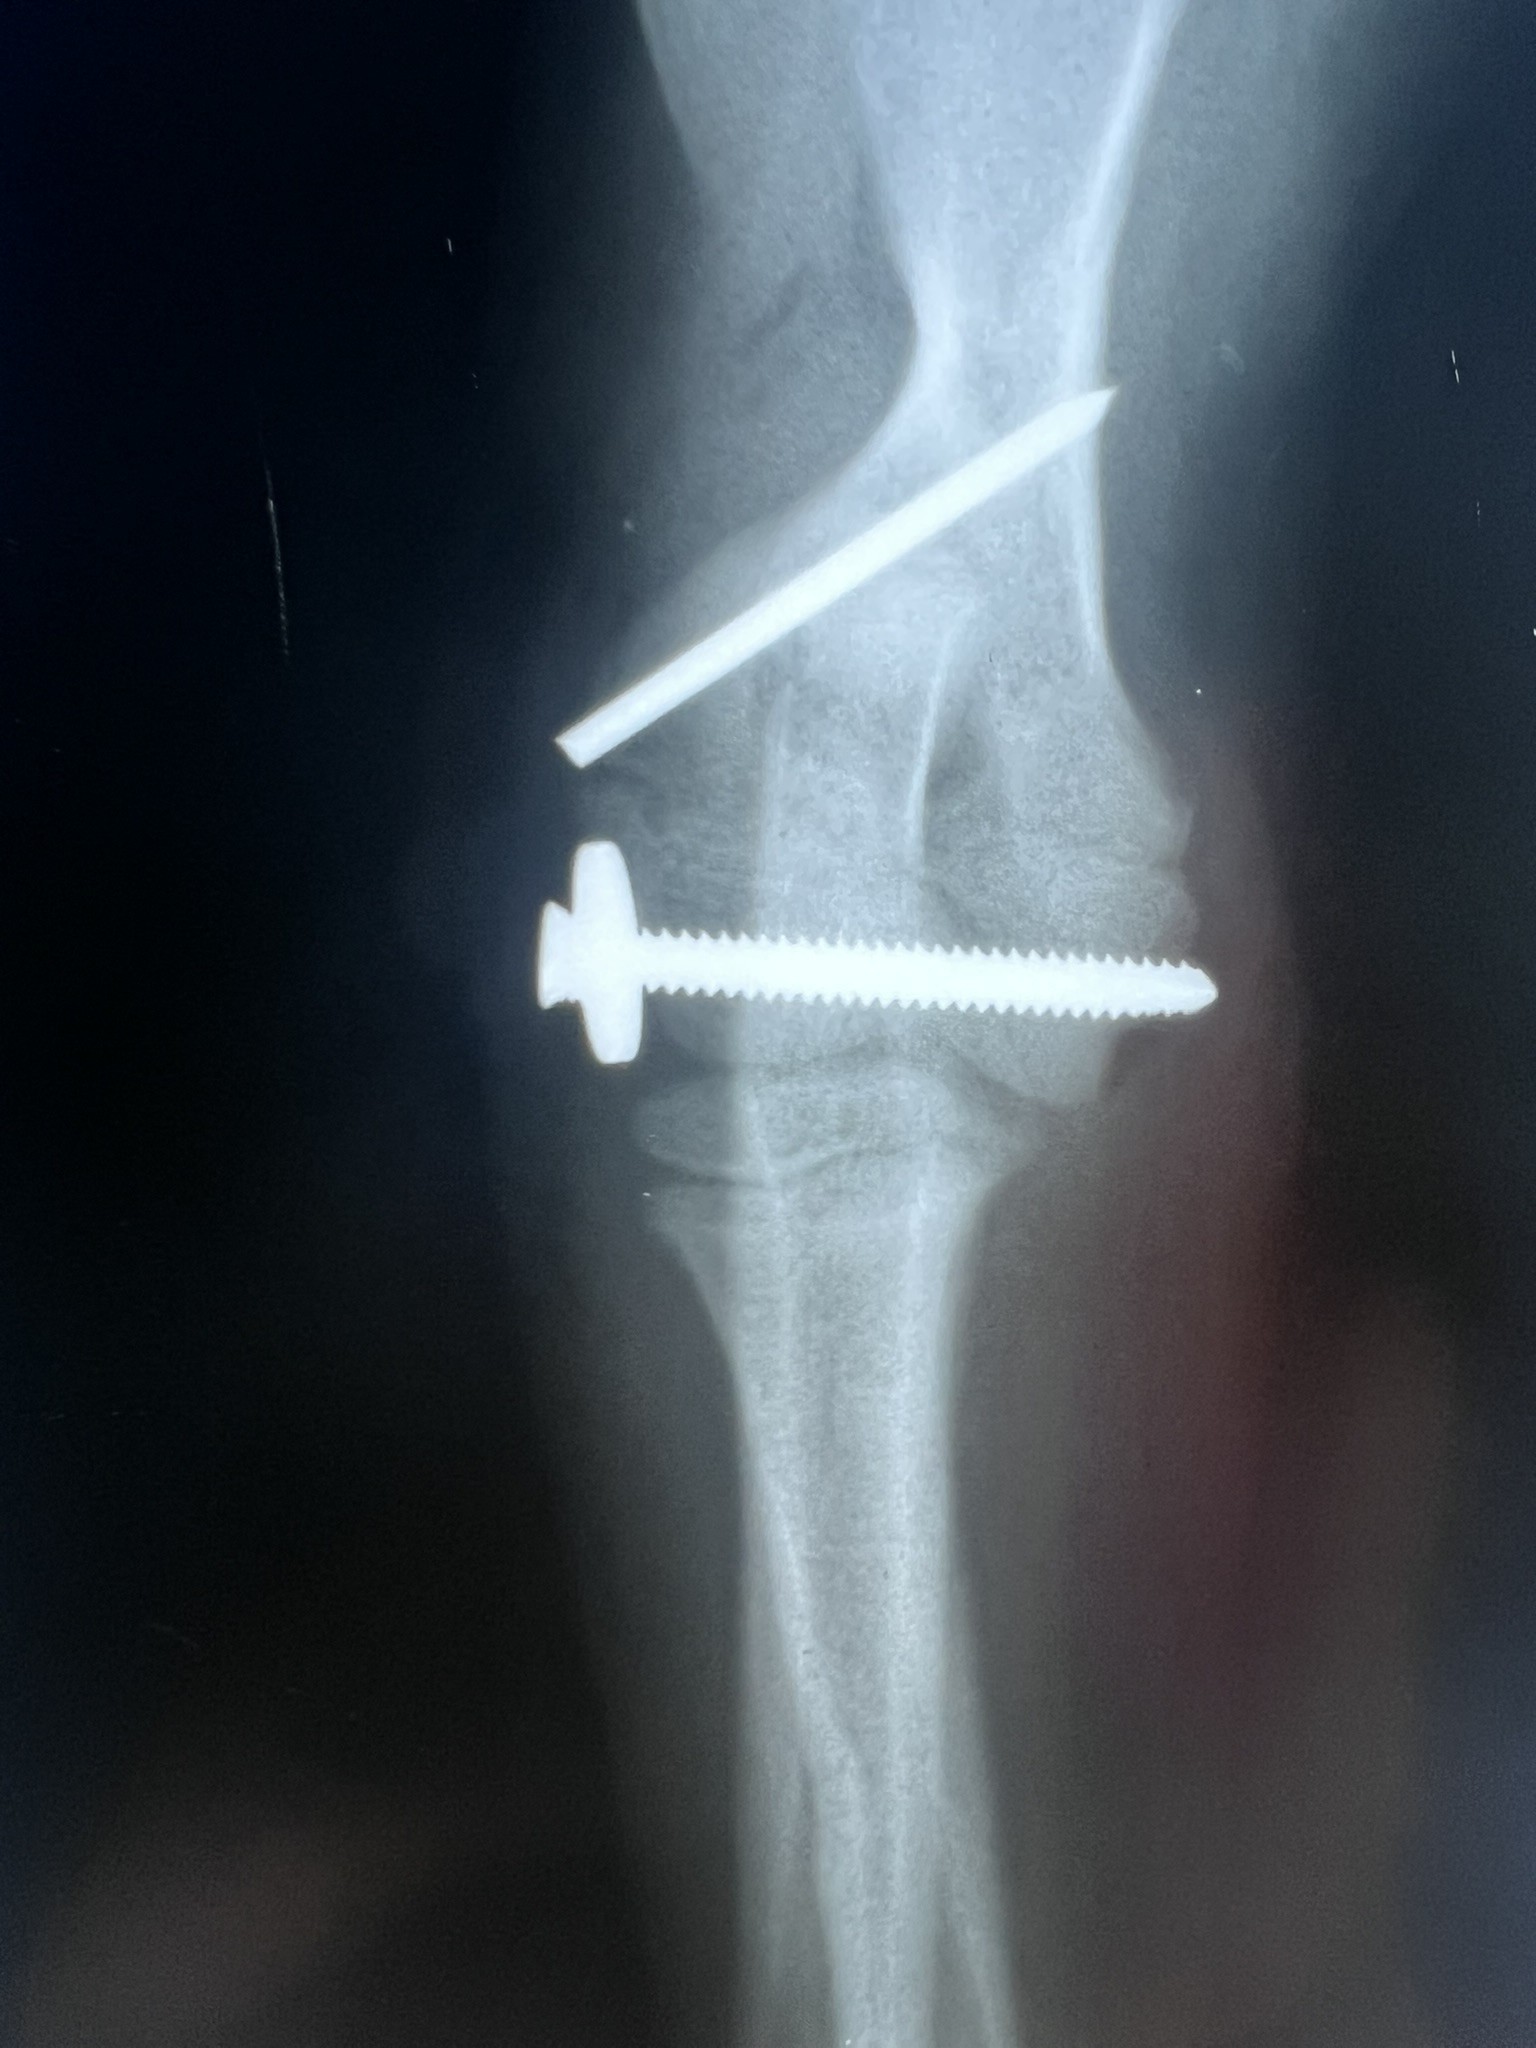

Screws, Pins and Wire

When fragments are very small or near the joint, we are limited to using small implants. These are relatively weak and more prone to failure or loosening. Often a bandage will be used post-operatively to help protect these repairs.

Articular humeral fracture in a puppy

Growth Plate tibial fracture in a puppy